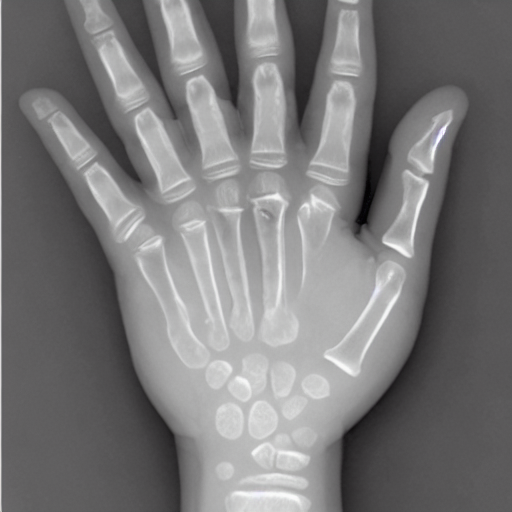

- The patient had residual paralysis of the hand after poliomyelitis. It was necessary to stabilize the thumb with reference to the index finger. This was accomplished by placing a graft from the bone bank between the first and second metacarpals. The roentgenogram shows the complete healing of the graft one year later.